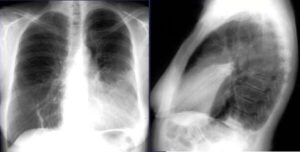

Что такое язычковая (лингвальная) пневмония

Легкое — это парный орган с 3 долями справа и 2 слева. Каждая доля имеет определенное количество сегментов (в правом и левом легких их по 10). В верхней части левого легкого расположены язычные сегменты (верхний и нижний). Лингвальная пневмония — это подвид левосторонней высокодолевой пневмонии, то есть, в отличие от нижнедолевой пневмонии, поражаются тростниковые сегменты …

Что такое односторонняя и двусторонняя пневмония

Двусторонняя пневмония у ребенка — опасная форма пневмонии, поражающая обе стороны легких, в отличие от односторонней пневмонии. Он может иметь бактериальную или вирусную природу. В нашей статье мы обсудим, что такое односторонняя и двусторонняя пневмония (ее еще называют двусторонней), симптомы, методы диагностики и лечения. Что это такое? Это инфекционно-воспалительный процесс в тканях легких, вызываемый атакой …